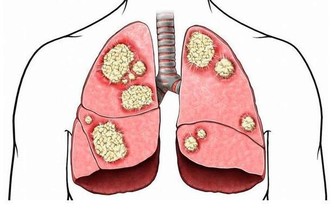

長期慢性智齒冠周炎還可能成為病灶感染的來源,導致關節炎或關節膿腫或其他器官的膿腫,甚至會導致心肌炎的可能。